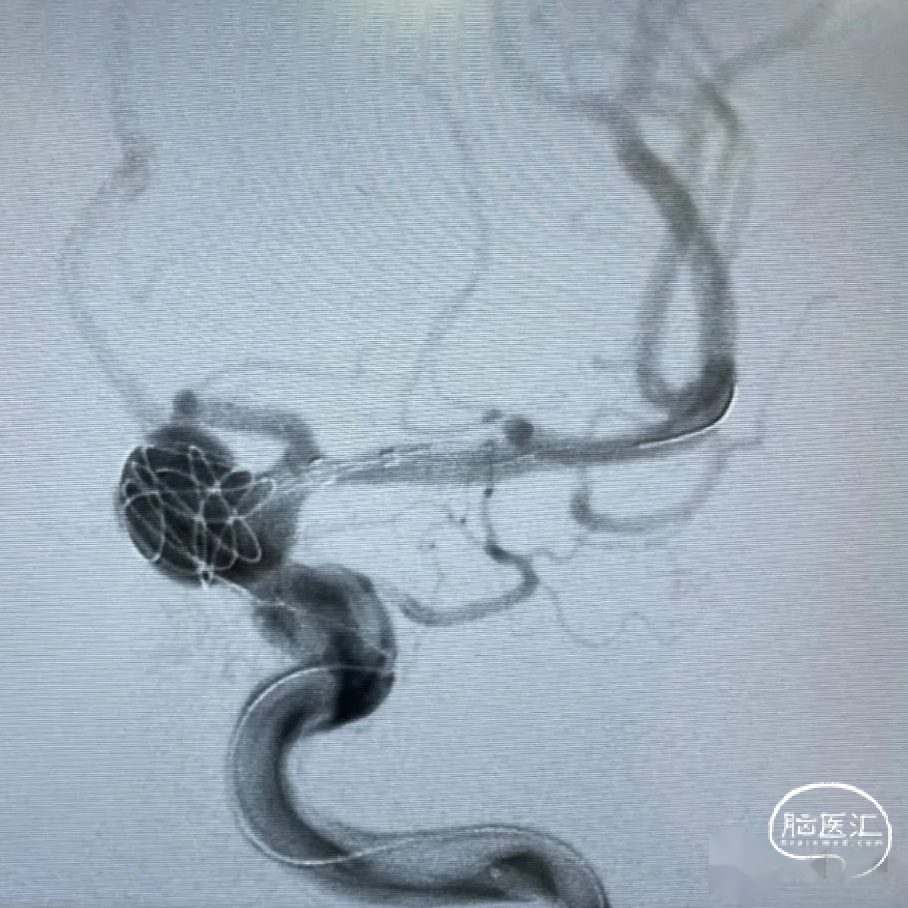

释放支架:

选用4.5mm*45mm Tubridge血流导向密网支架在远端预打开再回撤定位,缓慢推出支架进行头端锚定,支架头端位于大脑中动脉主干,造影观察后,继续缓慢释放Tubridge血流导向密网支架至瘤颈中段。确保支架充分贴壁,继续缓慢释放Tubridge血流导向密网支架,直至支架完全释放。

3

栓塞动脉瘤:

继续经弹簧圈微导管填入6mm*20cm、5mm*15cm弹簧圈。